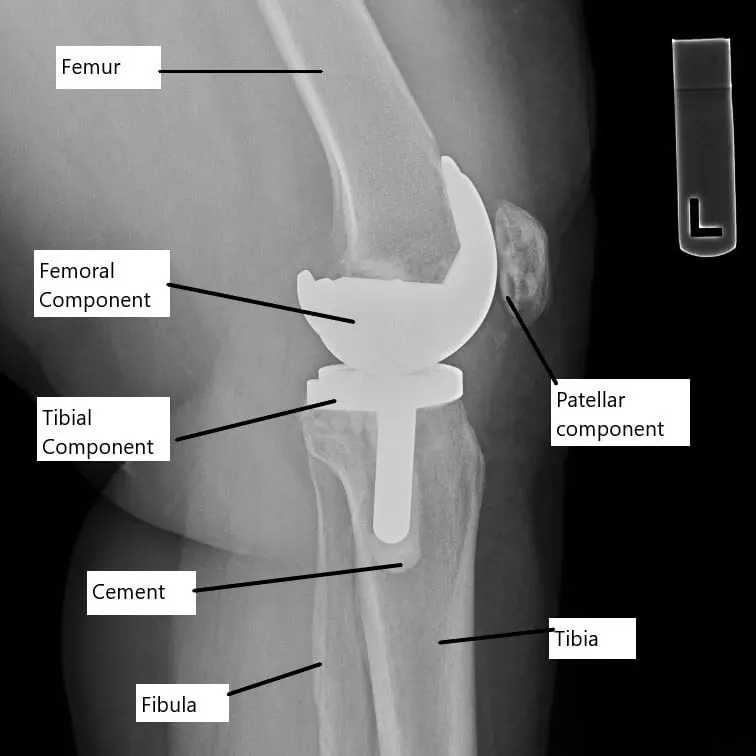

X-ray showing a total knee replacement.

In knee replacement surgery, the damaged ends of the femur (thigh bone) and tibia (shinbone) are removed and replaced with prosthetic components. A plastic insert is placed between the metal parts to reduce friction. This artificial joint is designed to mimic the natural function of the knee, allowing for smooth movement and weight-bearing. When pain persists, it may be due to issues with the implant or surrounding structures.